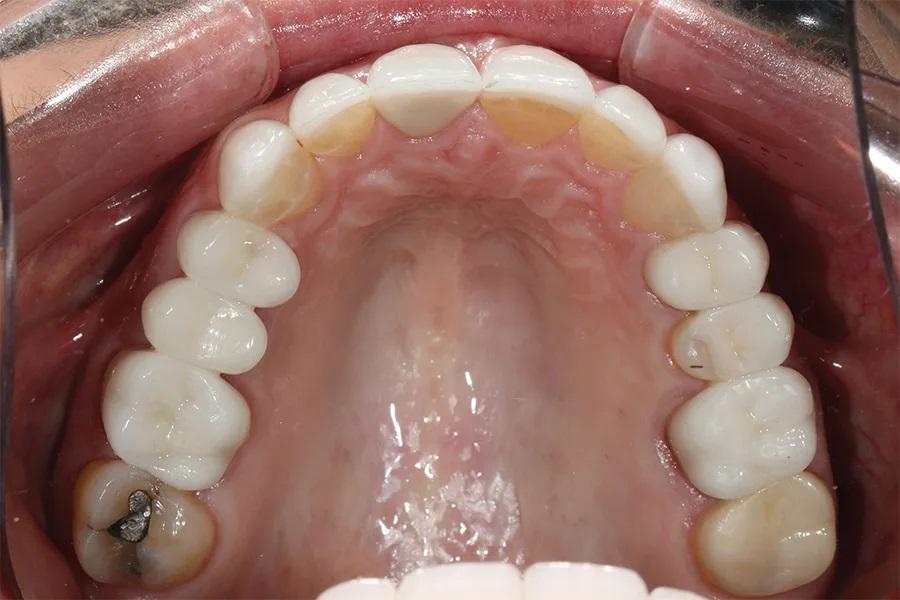

Стоматологический анамнез включал множественные пломбы и коронки. Пациентка сообщала о бруксизме (сжатии и скрежетании зубами), отмечая, что за последние 5 лет зубы стали короче и более изношенными. Было запланировано удаление зуба 15 в связи с переломом корня в области штифтово-культевой конструкции (фото 4). За последние 5 лет были заменены шесть разрушенных реставраций.

Фото 4. Окклюзионный вид верхней челюсти до лечения, демонстрирующий разрушенную временную конструкцию на имплантате в области зуба 15 и фрикционный износ на небной поверхности зубов 13–23.